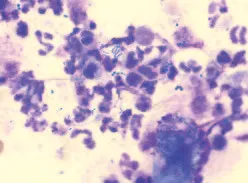

Cells: An occasional keratinocyte is to be expected, but in high numbers they may indicate seborrhea. Neutrophils with intracellular bacteria are typical in active ear infections with severe inflammation (Figure 4).

Multiple clusters of cocci and high numbers of neutrophils (modified Wright’s stain, original magnification, 100´; immersion oil)